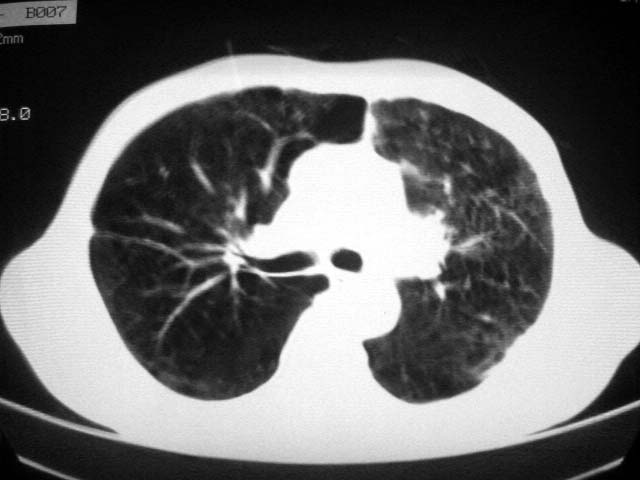

以下是引用zjzjr在2007-9-4 17:00:00的发言:[br]双上肺继发型结核伴左上肺空洞形成.慢性支气管炎伴肺气肿.

以下是引用liuzheng_9326在2007-9-4 16:23:00的发言:[br]痰检未见结核菌, 治疗后症状好转。图像符合陈旧性结核伴感染。